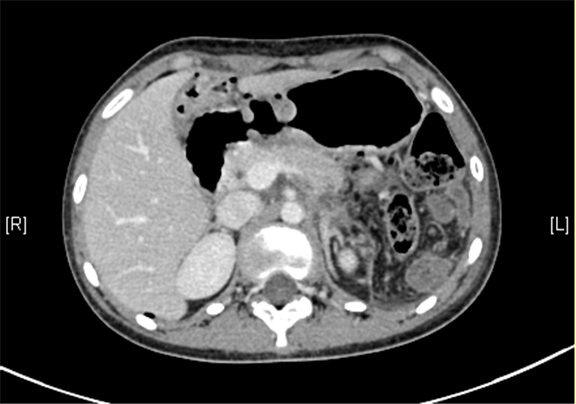

上腹部三维CT动态增强扫描: 胰腺体尾部类圆形软组织肿块,考虑实性假乳头状瘤可能性大。

术前CT检查:

动脉期